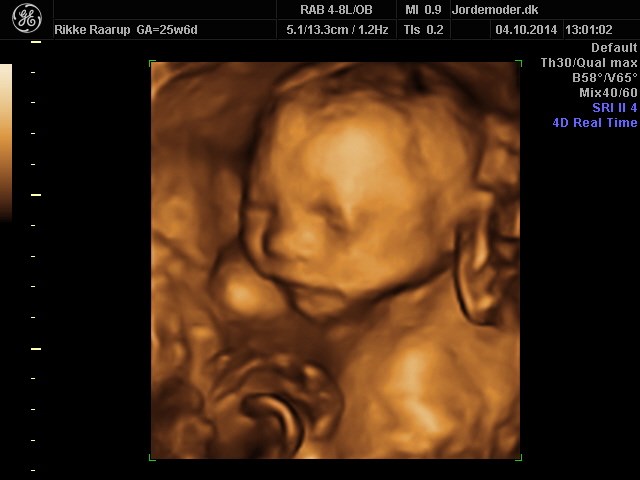

Siden har vi været til 3D/4D scanning hvor vi havde min mor og lillebrors storebror (

med. En scanning jeg var MEGET nervøs for, da vores familier stadig intet ved om at lillebror har været syg!

Scanningsdamen sagde intet om væske eller noget som helst, og lillebror vokser perfekt. Så det var enormt lettende. Han følger alle kurver rigtig flot og sparker derud ad!

Vedhæftede fotos (klik for at se i fuld størrelse)